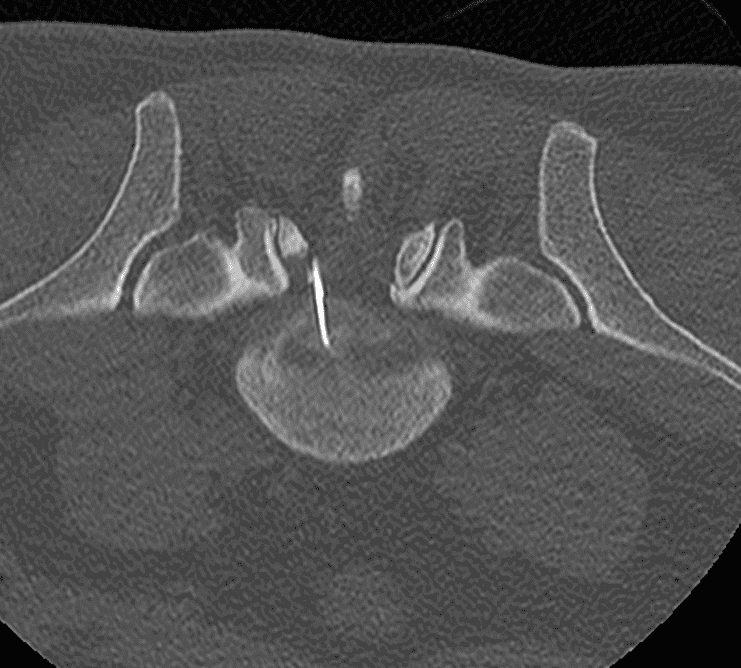

CT

Technique de vissage percutané des fractures du toit du cotyle